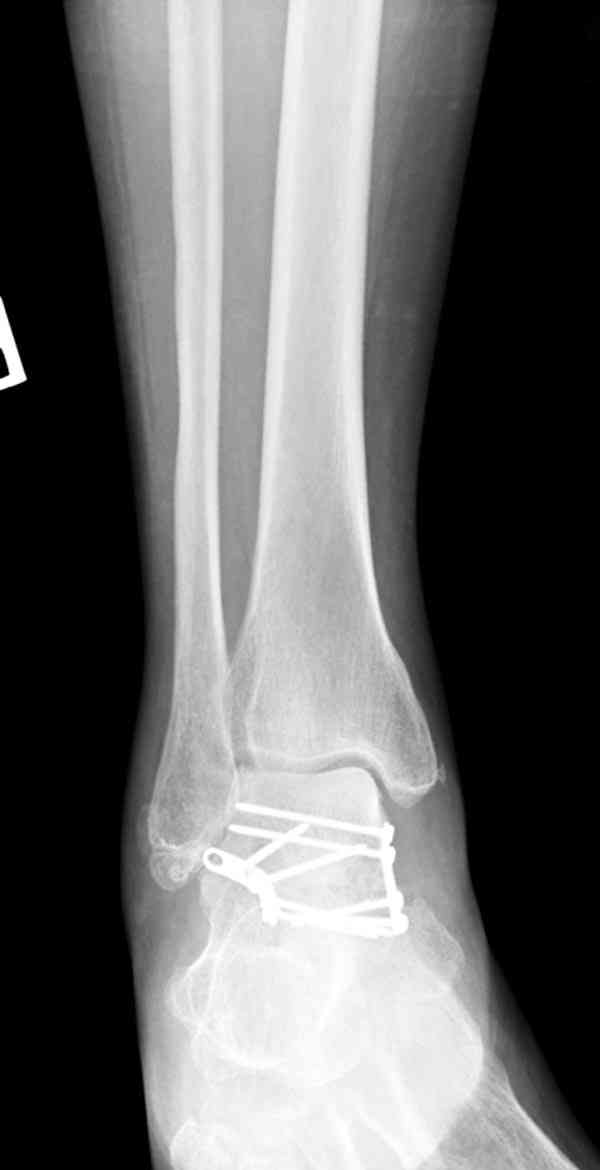

Случай с множественным оскольчатым переломом тарана оперированный из двойного доступа.

Через 2 мес.: